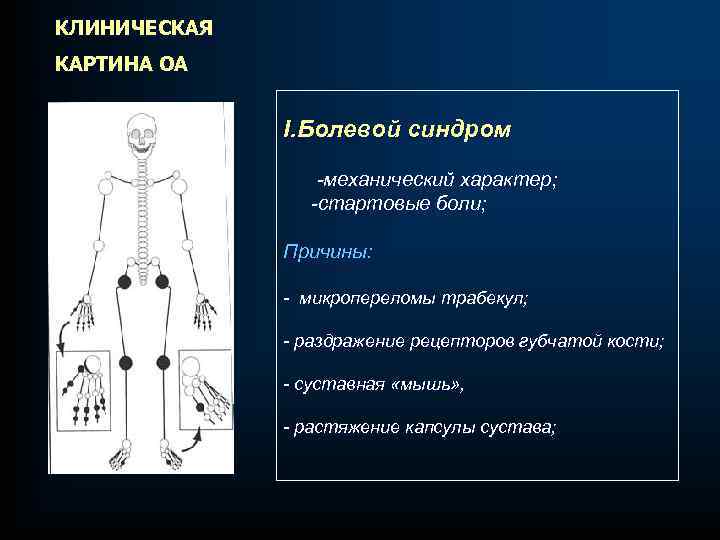

КЛИНИЧЕСКАЯ КАРТИНА ОА I. Болевой синдром -механический характер; -стартовые боли; Причины: - микропереломы трабекул; - раздражение рецепторов губчатой кости; - суставная «мышь» , - растяжение капсулы сустава;

КЛИНИЧЕСКАЯ КАРТИНА ОА I. Болевой синдром -механический характер; -стартовые боли; Причины: - микропереломы трабекул; - раздражение рецепторов губчатой кости; - суставная «мышь» , - растяжение капсулы сустава;